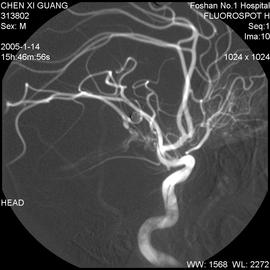

•血管造影:1至3小时

血管造影:注入造影剂有时会有温暖或灼热的感觉。造影剂可能引起恶心,呕吐,潮红,瘙痒或口苦等症状。在极少数情况下,人们会对造影剂产生严重的过敏反应,影响患者的呼吸和血压。造影剂也会引起肾脏问题,这种情况很少见,但在肾功能不全的患者中较常见。

该检查存在一种小风险的可能,就是在导管末端有可能会形成血凝块的,阻塞血管。导管损伤血管的风险也很小,但这可能导致内出血。如果按压时间过短,可能会导致创口出现血肿(皮肤下聚集大量血液)。除此之外,创口部位可能存在感染的几率。

你的身体可能会因为躺在操作台上几个小时而感到疼痛。